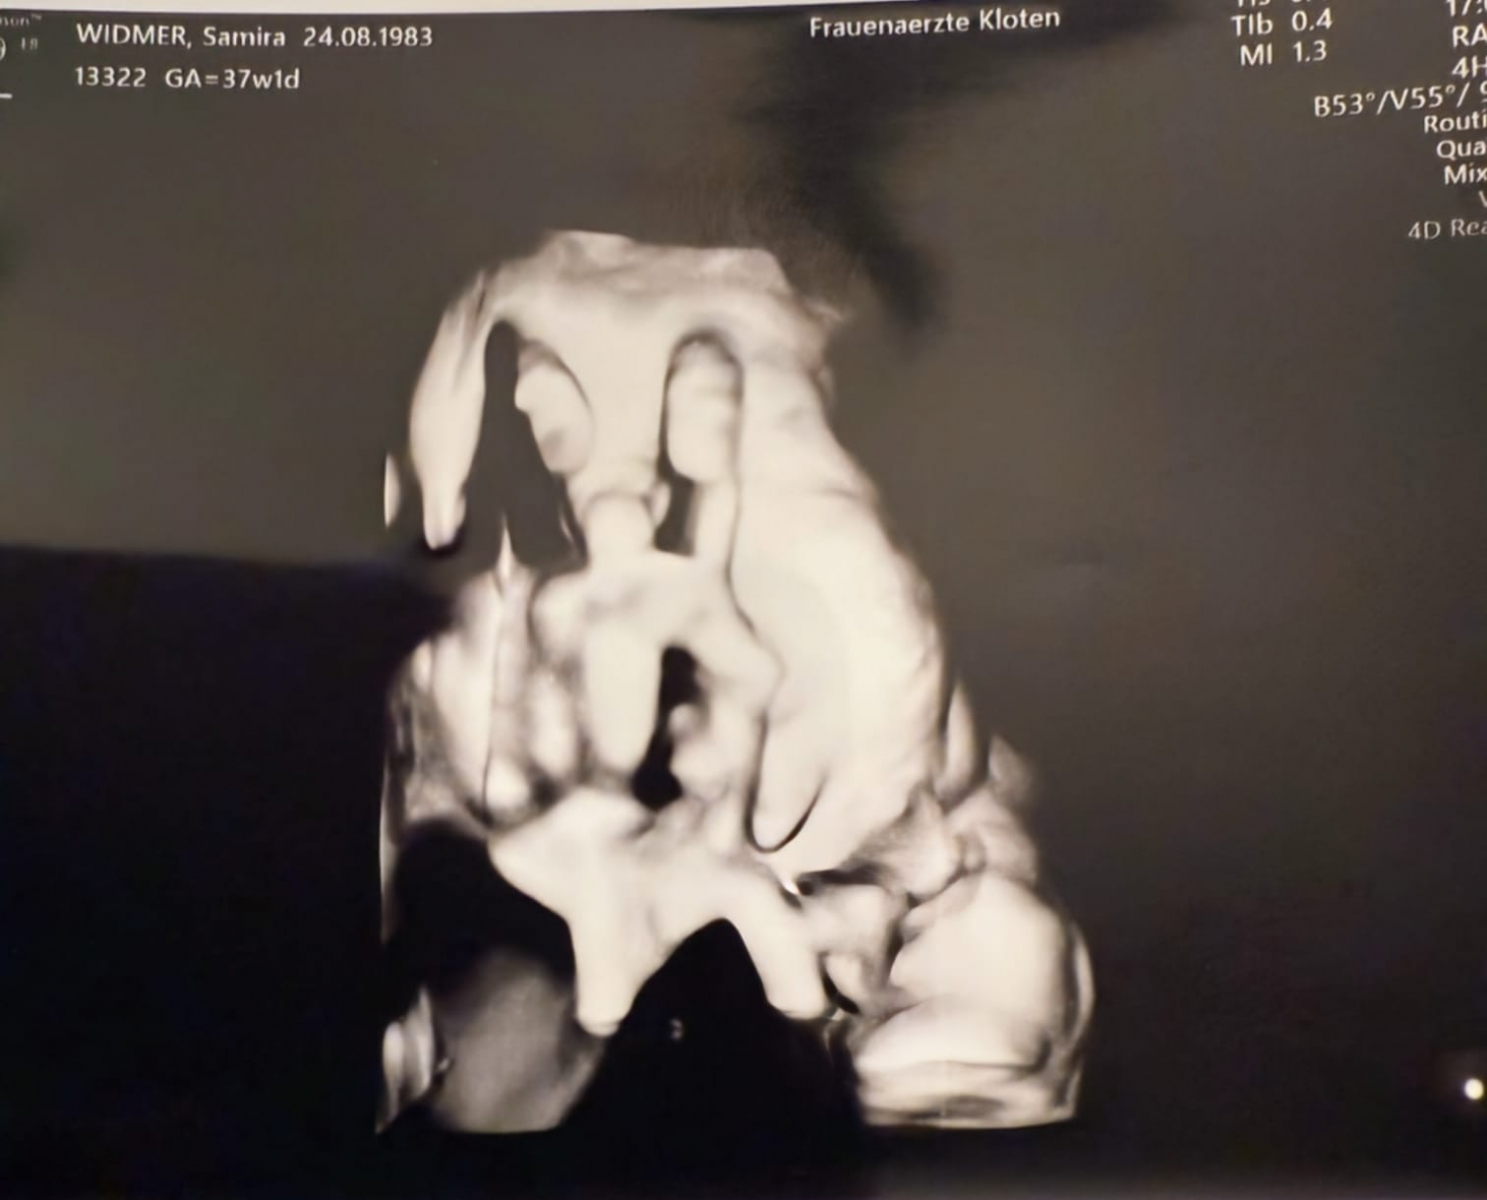

Kai (49) und Samira (40) aus der Schweiz kamen 2024 mit Kinderwunsch nach Vasektomie in unsere Praxis. Zuvor waren bereits mehrere Versuche der künstlichen Befruchtung (ICSI) sowie eine Hodenbiopsie erfolgt – ohne anhaltenden Erfolg.

Hier ging es auch mal schnell: Refi OP am 21.11.2017 - und war sogar etwas schwierig mit beidseitiger #Tubulovasostomie - dann kam schon schnell das Ultraschallbild und am 7.9.2018 wurde dann der kleine Maximilian geboren - also ein Treffer schon im 2. Zyklus....Glückwünsch vom ganzen Team!!!